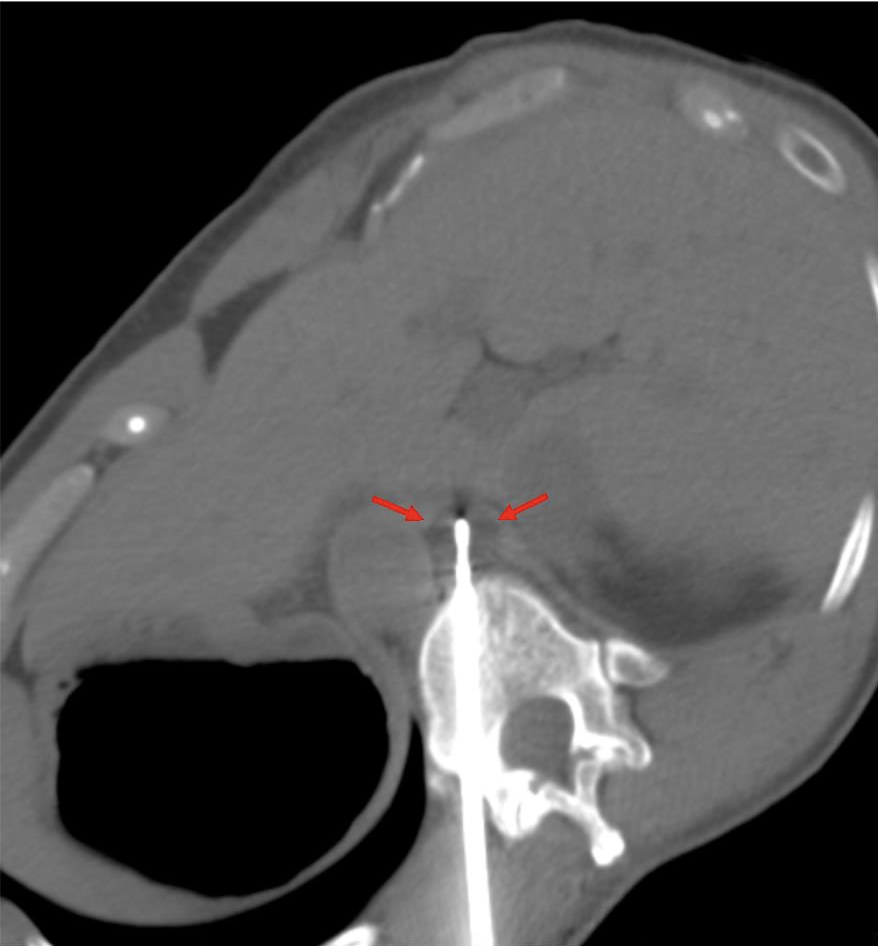

The patient was positioned prone oblique on the CT table (Figure 2). The procedure was performed under general anesthesia given the prone positioning, required precision for needle placement, and anticipated length of cryoablation. Under CT guidance, an 11-gauge bone access needle was advanced via a left transpedicular approach across the T12 vertebral body. Coaxial technique through this access was used to obtain both fine needle aspiration (FNA) and core biopsy samples (Figures 3-4). Immediate pathology assessment of the FNA samples confirmed metastatic adenocarcinoma. A single Endocare 17R cryoablation probe (Varian) was advanced through the 11-gauge access needle into the center of the nodal metastasis. Cryoablation was performed for 3 freeze-thaw cycles with intermittent CT monitoring to ensure adequate coverage of the lymph node and to minimize injury to the adjacent normal structures (Figures 5-6). All needles were removed, and the patient was extubated. After an uneventful overnight recovery, the patient was discharged home the following day.

FIGURE 5. Intraprocedure axial noncontrast CT image shows the therapeutic ice ball during freeze cycle of cryoablation (red arrows).